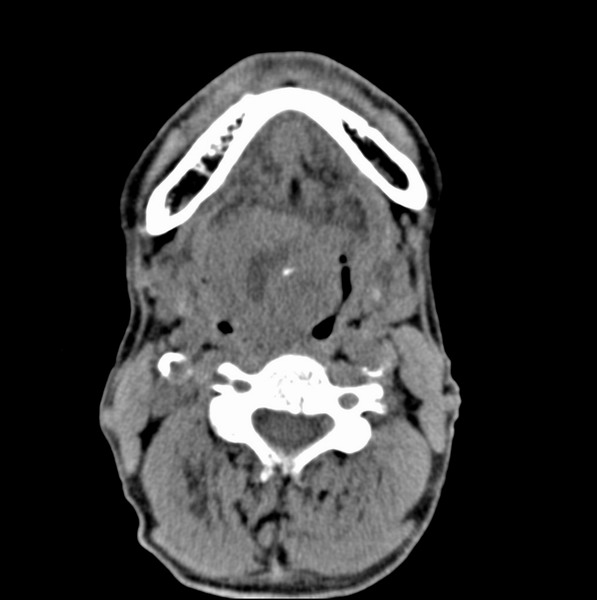

男、60、舌根肿物。

舌垂直肌和横肌影处肿块影,边缘不规则,咽腭扁桃体及舌下间隙脂肪影消失,病变侵及口咽。

考虑-----舌根癌

舌跟软组织肿块,较大有坏死,钙化。结合年龄一般是恶性肿瘤。

舌根部较大软组织肿块,其内见坏死低密度区及钙化影;考虑舌根癌可能。